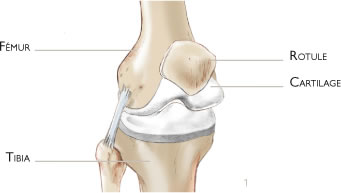

Le genou correspond à l’articulation entre le fémur et le tibia. La rotule est une troisième partie osseuse qui est située en avant et qui fait partie de l’articulation. Les surfaces articulaires de glissement sont recouvertes de cartilage (figure 1). De nombreux muscles et tendons entourent cette articulation et permettent d’étendre et de plier le genou.